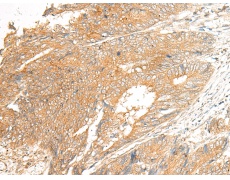

IHC positive control: |

Human colorectal cancer and Human cervical cancer |